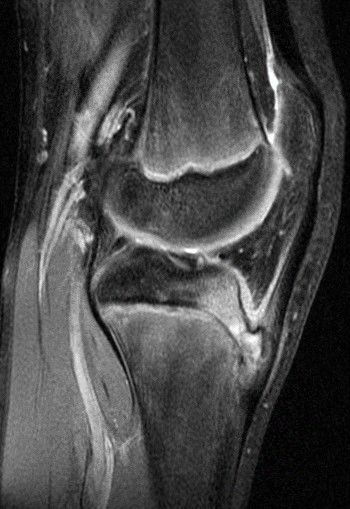

三、MRI

分为五期:正常、早期、进展期、终末期、愈合期。

1.正常:尽管患者已有症状,但是MRI显示正常;

2.早期:无炎症表现,无二次骨化中心撕脱;

3.进展期:二次骨化中心部分软骨撕脱;

4.终末期:可见游离骨片;

5.愈合期:胫骨结节骨性愈合,无游离骨片。

国外一些研究者认为MRI检查是诊断胫骨结节骨软骨炎最好的方法,特别是能发现早期和进展期病灶,MRI检查可以反映胫骨结节骨软骨炎疾病过程,而其他检查方法无能为力。但是MRI检查比较昂贵且不普及这样就限制了它在国内诊断胫骨结节骨软骨炎的应用。